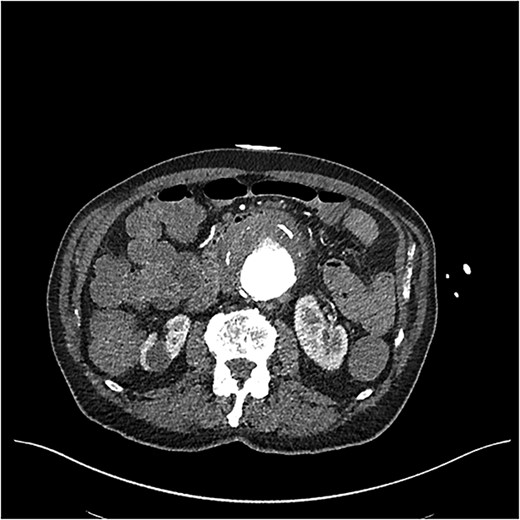

CT showed a likely AEF associated with a 7 cm inflamed aneurysmal sac posterior to the third part of the duodenum (Fig. 1). While no active bleeding was seen, large clots were present in the stomach and colon. Goal-directed resuscitation was commenced and he was transferred to a tertiary centre. After general and vascular surgical review, the patient proceeded to theatre for urgent endovascular aneurysm repair (EVAR) and duodenal repair.

CT angiogram on initial presentation demonstrating an aneurysmal abdominal aorta but no contrast extravasation.